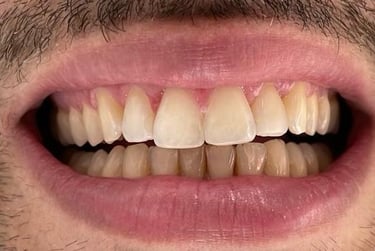

Aspecto Clínico Final - Fotografias originais — nenhuma contém retoques — A cor dos dentes é escolhida de acordo com o gosto e a preferência estética de cada paciente.

Depois